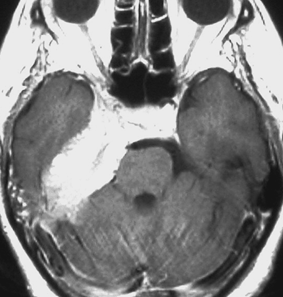

典型的な髄膜腫

この髄膜腫は中程度の大きさのものです。円蓋部髄膜種という最も多い最も手術の簡単なタイプです。麻痺や失語症やてんかんなどの症状はありません。とても美しくて若い女性の髄膜腫でしたが,子供に遺伝はしませんし,癌などと違ってタバコなどこれといった原因がなくて発生するものです。

MRIでの髄膜腫の見え方は撮影の仕方によっていろいろです。左からT1強調画像,T2強調画像,フレア画像といいます。腫瘍の横に小さく白い領域がありますが,これは脳の腫れた部分で脳浮腫といいます。髄膜腫があると周囲に脳浮腫が生じることがあります。

最も見やすいのが,ガドリニウム造影剤を注射して撮影するものです。一般的に髄膜腫は造影剤で白く映し出されます。この腫瘍は左脳側にあります。MRIの軸面という輪切りの写真では左右が逆になりますから注意してください。脳を下から見た図になっています。MRIはいろいろな方向から腫瘍を見ることができますが,右は冠状断という正面から見た図です。よく見ると腫瘍の上と下のはじっこに線状に糸を引いたように造影される部分があります。これをテールサイン(しっぽのサイン)といいます。腫瘍が硬膜に沿って延びている可能性があることを示しています。